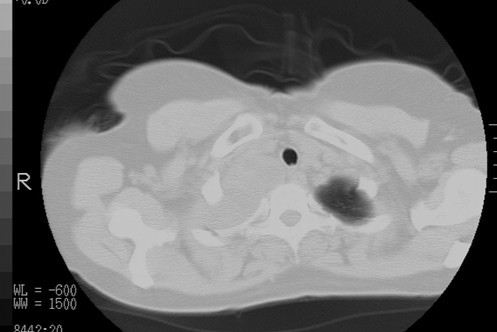

以下是引用随光逐影在2010-3-1 8:36:00的发言:[br]右上纵隔囊性占位性病变,考虑支气管囊肿,不排除神经源性肿瘤。